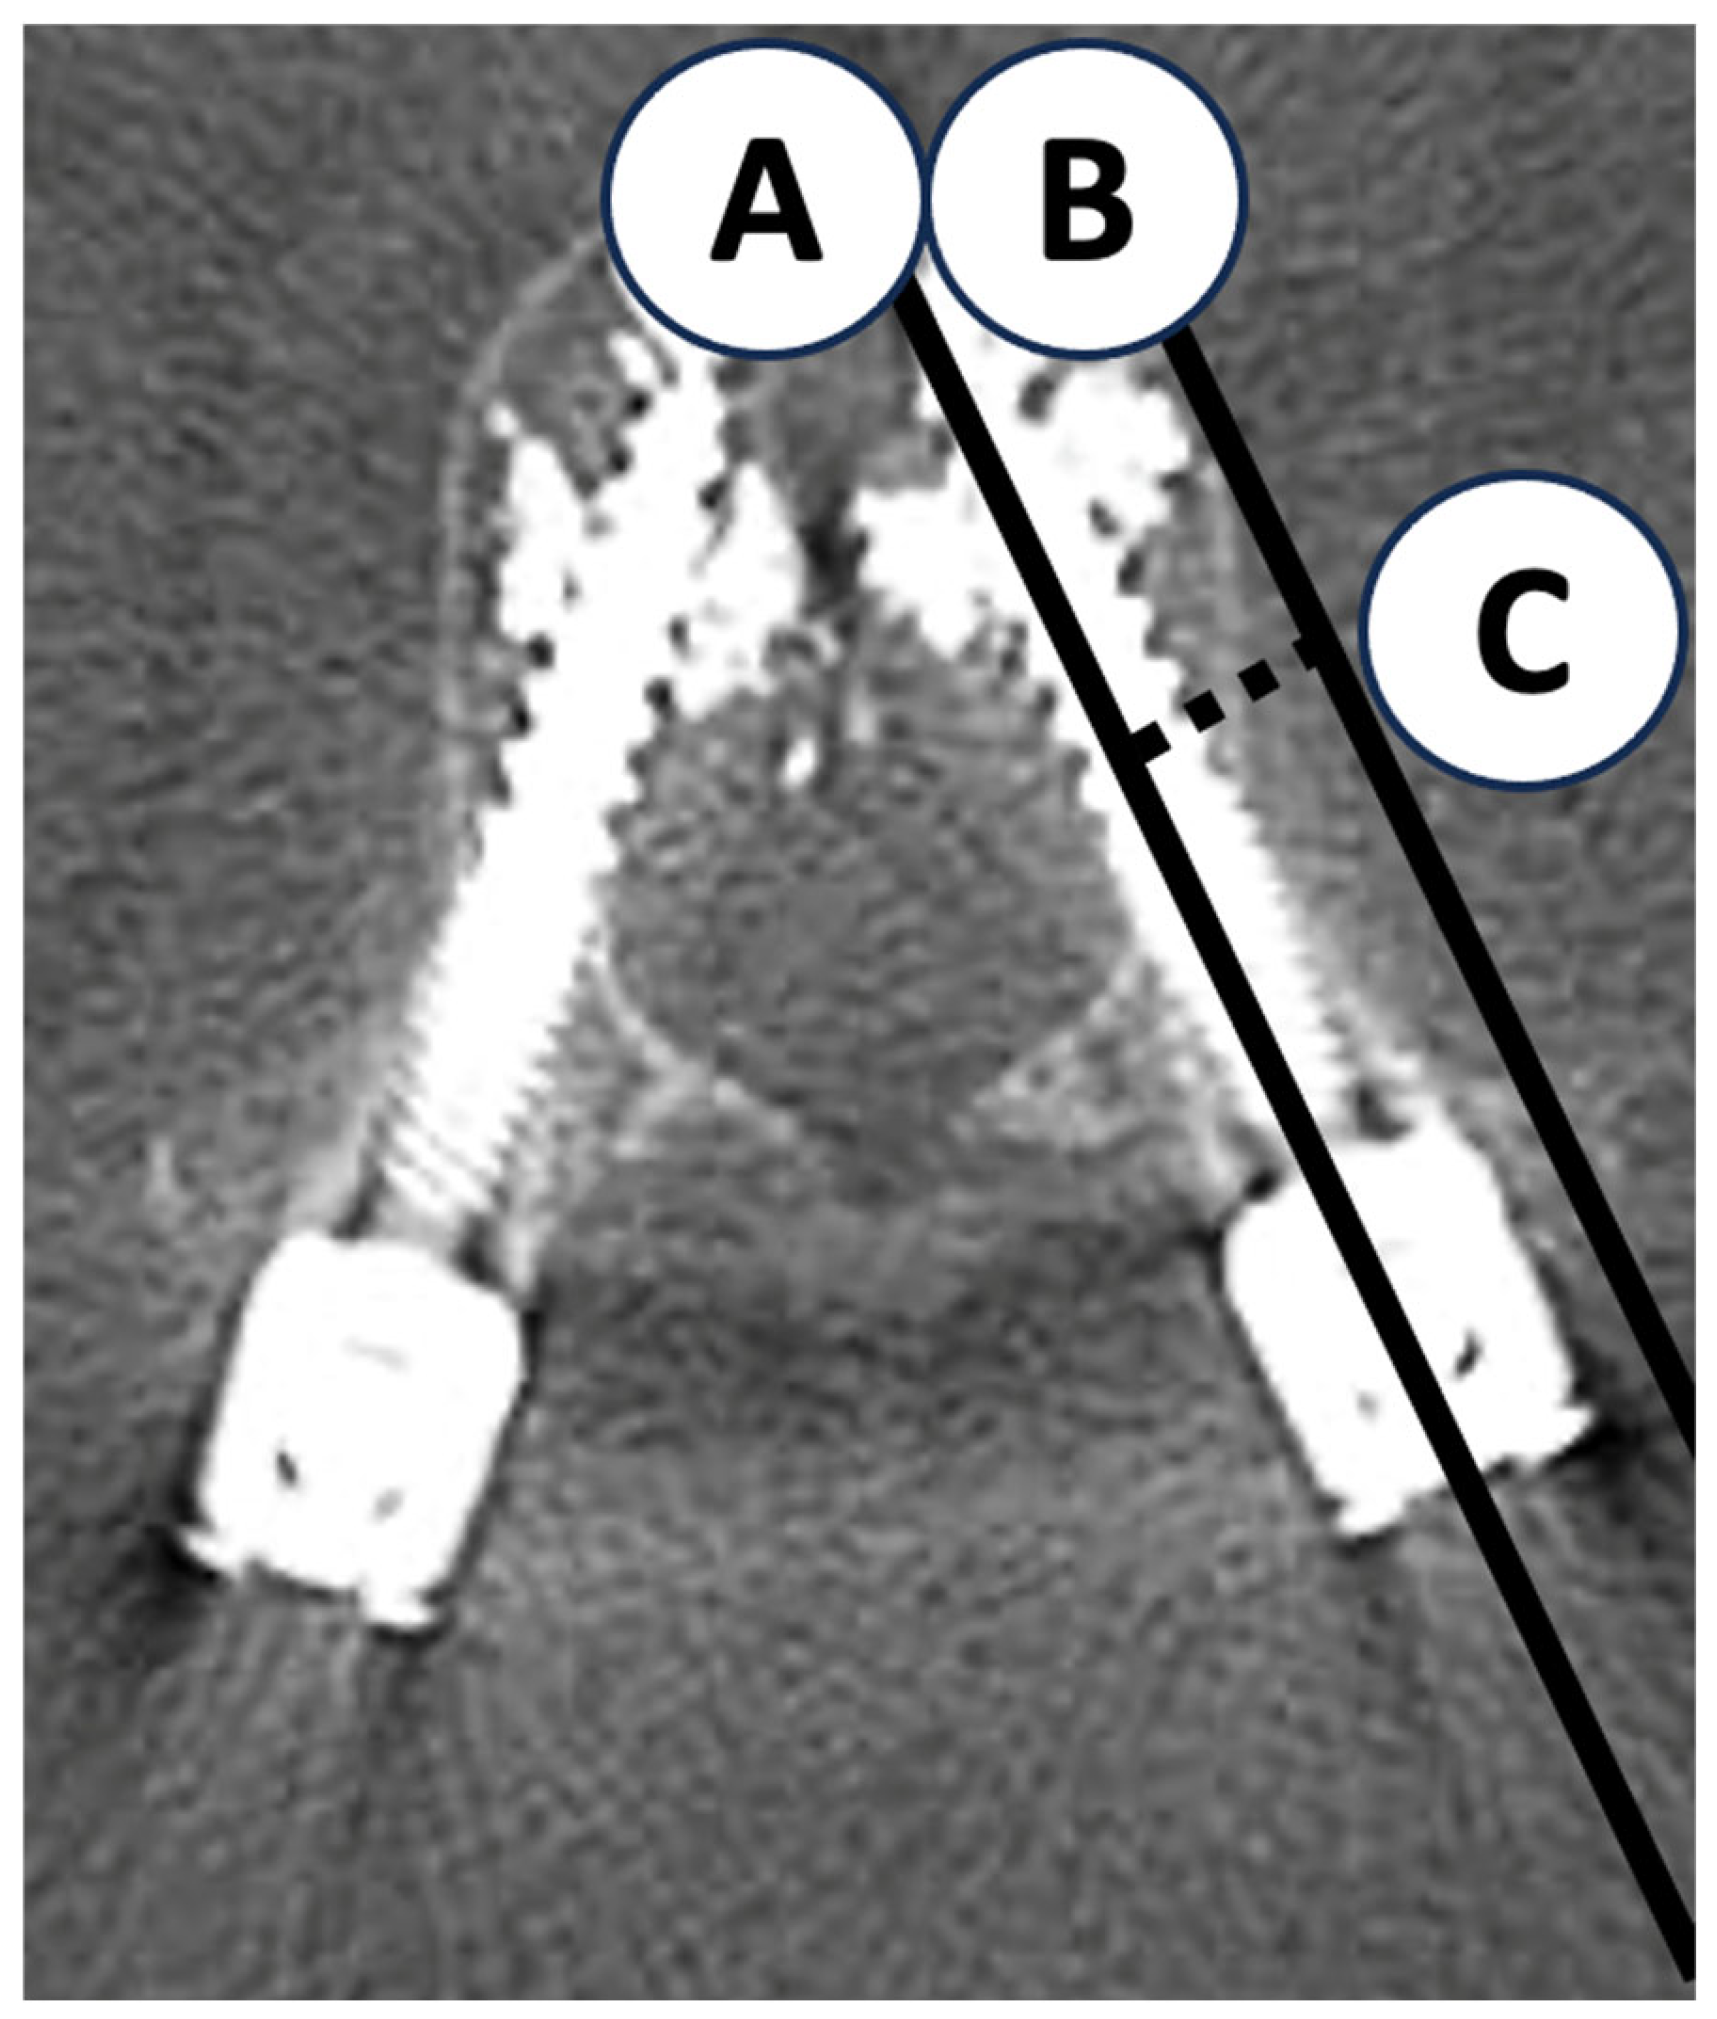

2.5. Quantitative Measurements

| Lateral cortical wall distance (per 1 mm) | 0.582 | 0.506–0.669 | <0.001 | 0.547 | 0.469–0.638 | <0.001 |

| Lateral cortical wall distance | 0.842 | 0.789–0.896 | <0.001 | ≤9.21 | 0.845 | 0.719 |